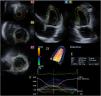

Three-dimensional speckle-tracking echocardiographyFor the 3D-STE examinations, the same Toshiba Artida™ system was used, with a PST-25SX matrix- array transducer (Toshiba Medical Systems, Tokyo, Japan).7 In each case, a pyramid-shaped full-volume 3D dataset was obtained. The complete dataset consisted of six wedge-shaped subvolumes, which were recorded during six RR intervals and a single breath-hold. The subvolumes were set to be as narrow as possible to improve spatial resolution, thus improving later endocardial border delineation. The recorded datasets were analyzed offline using the supplied 3D Wall Motion Tracking software, version 2.7 (Toshiba Medical Systems, Tokyo, Japan). From the datasets, the software automatically reconstructed apical 4-chamber and 2-chamber views, then the reader specified the three cross-sectional planes manually, using the guide planes to help standardize LV measurements. After setting up the planes, the reader then specified the septal and lateral parts of the mitral annulus and the LV apex, after which the software automatically detected the endocardial border and created a 3D LV cast (Figure 1).

Three-dimensional speckle-tracking echocardiographic study of an acromegalic patient. Apical 4-chamber view (A) and apical 2-chamber view (B) are automatically selected by the software. Cross-sectional planes are at the apical (C3), midventricular (C5) and basal (C7) left ventricular (LV) levels. The three-dimensional LV model (D) and the corresponding volumetric parameters (E) are shown along with segmental LV radial strain curves (F).